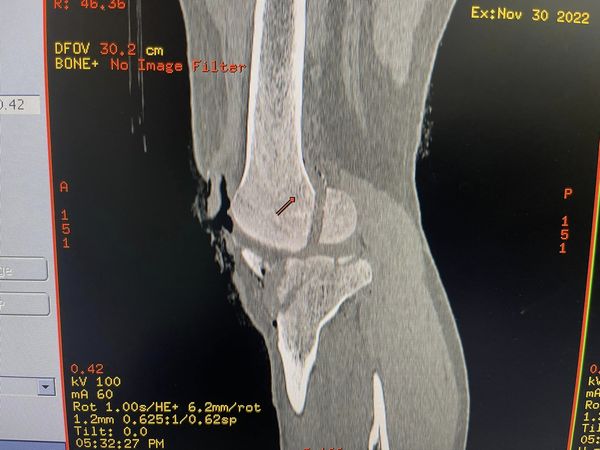

A 22-year-old western dance and music teacher with an open fracture of the distal femur, and proximal tibia, a large chunk of patella lost on the street, and a patellar tendon torn and tattered with a grossly contaminated wound filled with debris and paint flakes from his bike. This is the sort of thing that is mainly treated with prayers (classic Bollywood style “dawa nehi dua ki zaroorat”) however the closest 2nd most effective thing is ilizarov. These are versatile ringfixators that take care of such extensive injuries while giving the soft tissue and skin a fighting chance to be repaired and healed.